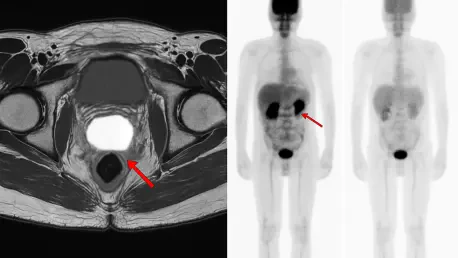

The transformative potential of PSMA PET/CT imaging lies in its fundamentally different mechanism. This advanced diagnostic tool utilizes a unique radioactive tracer meticulously designed to bind to the prostate-specific membrane antigen, a protein that is heavily overexpressed on the surface of most prostate cancer cells. This targeted binding process allows the scan to illuminate even minuscule clusters of malignant cells that would remain completely invisible on standard scans. The result is a clear and precise map of the recurrent disease, providing clinicians with invaluable information. It reveals whether the cancer is confined to the original prostate bed, has migrated to nearby pelvic lymph nodes, has metastasized to distant sites like bones, or is not yet detectable. This detailed anatomical information provides an unprecedented level of insight, forming the basis for a truly personalized treatment strategy that moves far beyond the limitations of older technologies.

Armed with the detailed map provided by a PSMA PET/CT scan, oncologists can pivot from a generalized treatment plan to a highly individualized therapeutic approach. The comprehensive study meticulously documented how this precise imaging directly informed critical clinical decisions that were tailored to each patient’s unique disease presentation. For instance, the scan results guided the determination of the radiation field, helping physicians decide whether to limit treatment to the prostate bed or expand it to encompass the whole pelvis. It also enabled the use of dose escalation, a technique where a higher, more potent dose of radiation is delivered directly to tumors made visible by the scan. Furthermore, the decision to add androgen deprivation therapy, a treatment with considerable side effects, was no longer a default but a targeted choice reserved for patients where imaging confirmed the cancer had spread, ensuring that only those who would truly benefit received it.